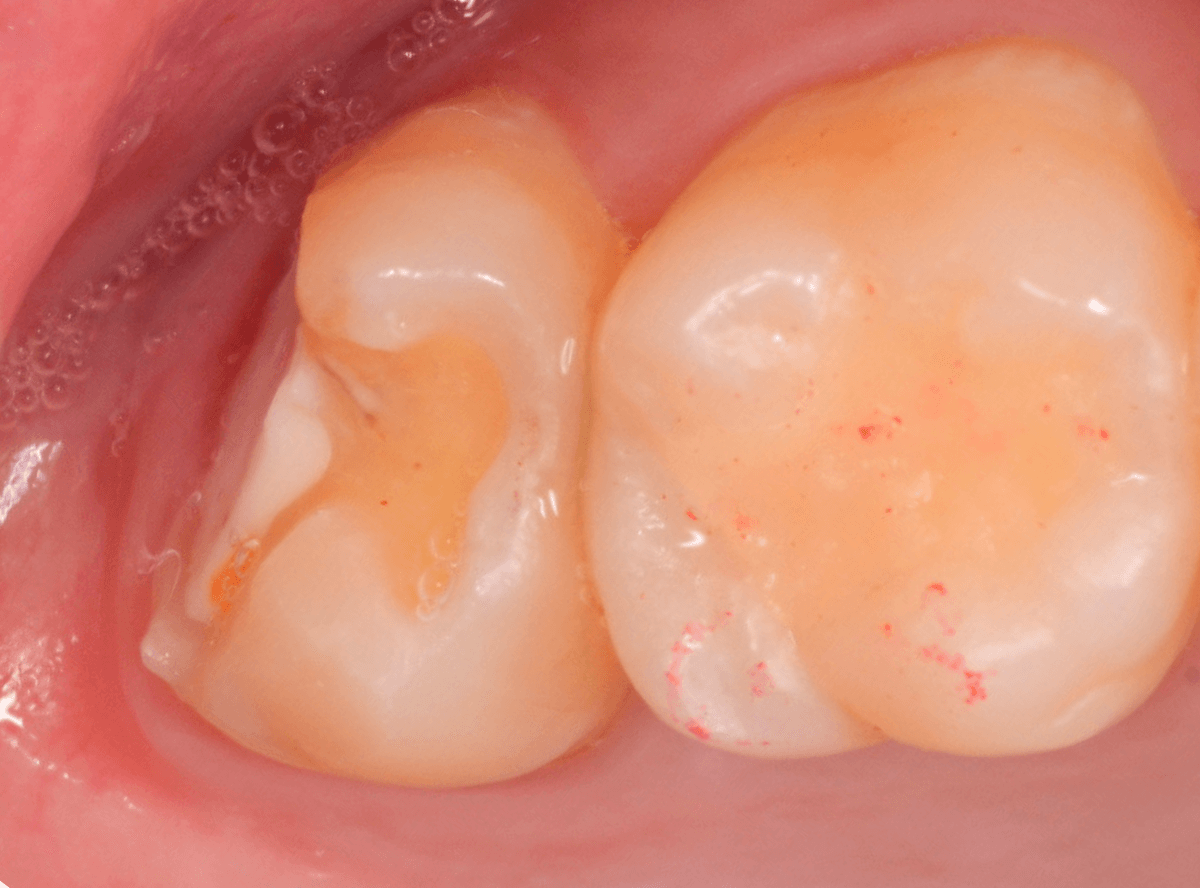

Case.4 2年間メンテナンスを中断している間に、深く虫歯が進行!

定期メンテナンスを2年間中断後に、来院された患者さんです。

見た目は手前の歯との間の小さな虫歯に見えますが、

「普段は痛くない」

「食事の時に物がつまる」

「物がつまった時に噛むと痛い」

・・・と、自覚症状は乏しいが、実際は大きな虫歯の場合の症状あるあるの訴えでした。

レントゲン写真で虫歯の状況を確認します。

赤い線が虫歯の部分、青い線が歯の神経の部分です。

思った通り、入り口の小さなすき間の中は、神経まで達してしまいそうな大きな虫歯になっていました。

歯を削り始めると、すぐに大きな穴が出てきました。

ある程度虫歯を除去したところで、う蝕検知液で染め出してチェックします。

まだまだ虫歯が残っていますね。

取り残しがないように、しっかり除去する必要があります。

虫歯を全て除去したところです。

神経が少し見えるところまで虫歯が進行していました。

神経を保護するお薬をつめた後、蓋をしてしばらく痛みが出ないか、経過観察します。

痛みが出て止まらないようでしたら、神経を除去する治療が必要になります。

定期メンテナンスを中断しなければ、このような状況にはならなかった事が本当に悔やまれます。

しばらく経過観察後、幸運にも特に症状なく経過しましたので、型どりをして、つめもの(メタル・インレー)で修復する事ができました。

この後、サボらず定期メンテナンスに来院いただくよう、念を押して治療終了となりました。